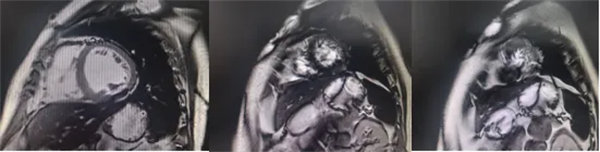

在常規心臟MRI檢查中,醫學影像科發現患者心肌異常表現,考慮鐵過載性心肌病,為明確診斷要進一步加做鐵定量技術,加掃T2 mapping序列。CMR鐵定量技術是目前評估心肌鐵含量的“金標準”,能夠快速、無創、精準量化心肌內鐵沉積程度,檢查結果提示患者局部心肌T2*值顯著低于正常范圍,符合鐵過載性心肌病的診斷標準。

基底部、中間部及心尖部 局部心肌T2*值明顯減低T2* 10-20/s, 部分小于10/s

心肌信號局部減低 呈現“黑色心肌”表現,這是由于鐵沉積導致局部磁場不均勻,引起信號丟失(失相位)。